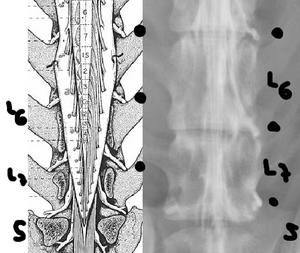

![]() por Juan M. Griñán. Veterinario ![]() comparativa entre una mielografía (mostrando la aguja) y una resonancia magnética, secuencia SE T1w (mostrando donde está el saco dural, sitio para la inyección del contraste). Nótese la extravasación del contraste yodado en la mielografía. | |||||||||